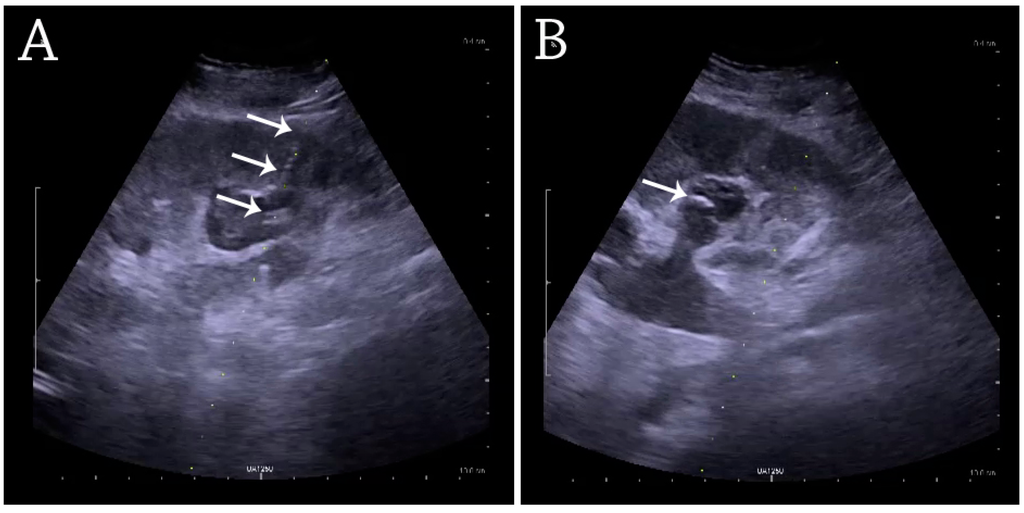

For percutaneous nephrostomy and abscess drainage, either the one-step or the Seldinger technique is used. Using the Seldinger technique, the cavity is punctured with a sharp hollow needle, called a trocar. A round-tipped guidewire is then advanced through the lumen of the trocar, and after withdrawal of the trocar, a catheter or nephrostomy can be inserted over the guidewire to ensure correct placement. The one-step technique is when insertion of the drain or nephrostomy is done without the aid of a guidewire [4]. The interventions are performed under local anesthesia and in a sterile setup. The procedures can be carried out with or without needle guidance according to preference, experience and setup (Figure 29) [33,34].

Figure 29. (A) Percutaneous nephrostomy tube placed through a calyx in the lower pole of a kidney with hydronephrosis. (B) The pigtail catheter is placed in the dilated calyx. The tube in (A) and the pigtail in (B) are marked with white arrows.